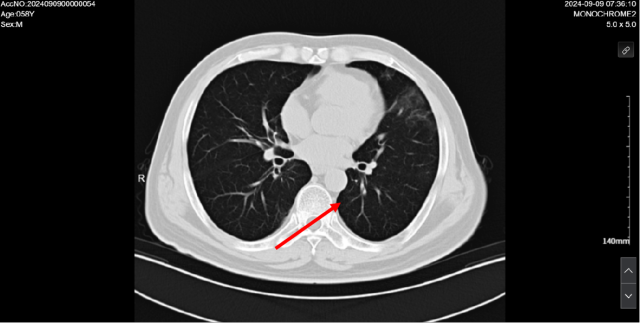

伏罗尼布治疗后,2024-09-09 复查CT

1. 考虑双肺炎症改变,较前范围减小,建议复查

2. 双肺多发结节,较前减小。

3. 双肺多发纤维灶。

4. 心包积液。

5. 肝内多发低密度病变,结合病史,不除外转移瘤可能,较前部分减小:建议必要时 CT 增强扫描进一步检查。

6. 考虑:肝左叶囊肿。